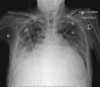

An Audaciously Aneurysmal Atrium

Keywords: Echocardiography; Imaging; Mitral stenosis; Rheumatic heart disease.